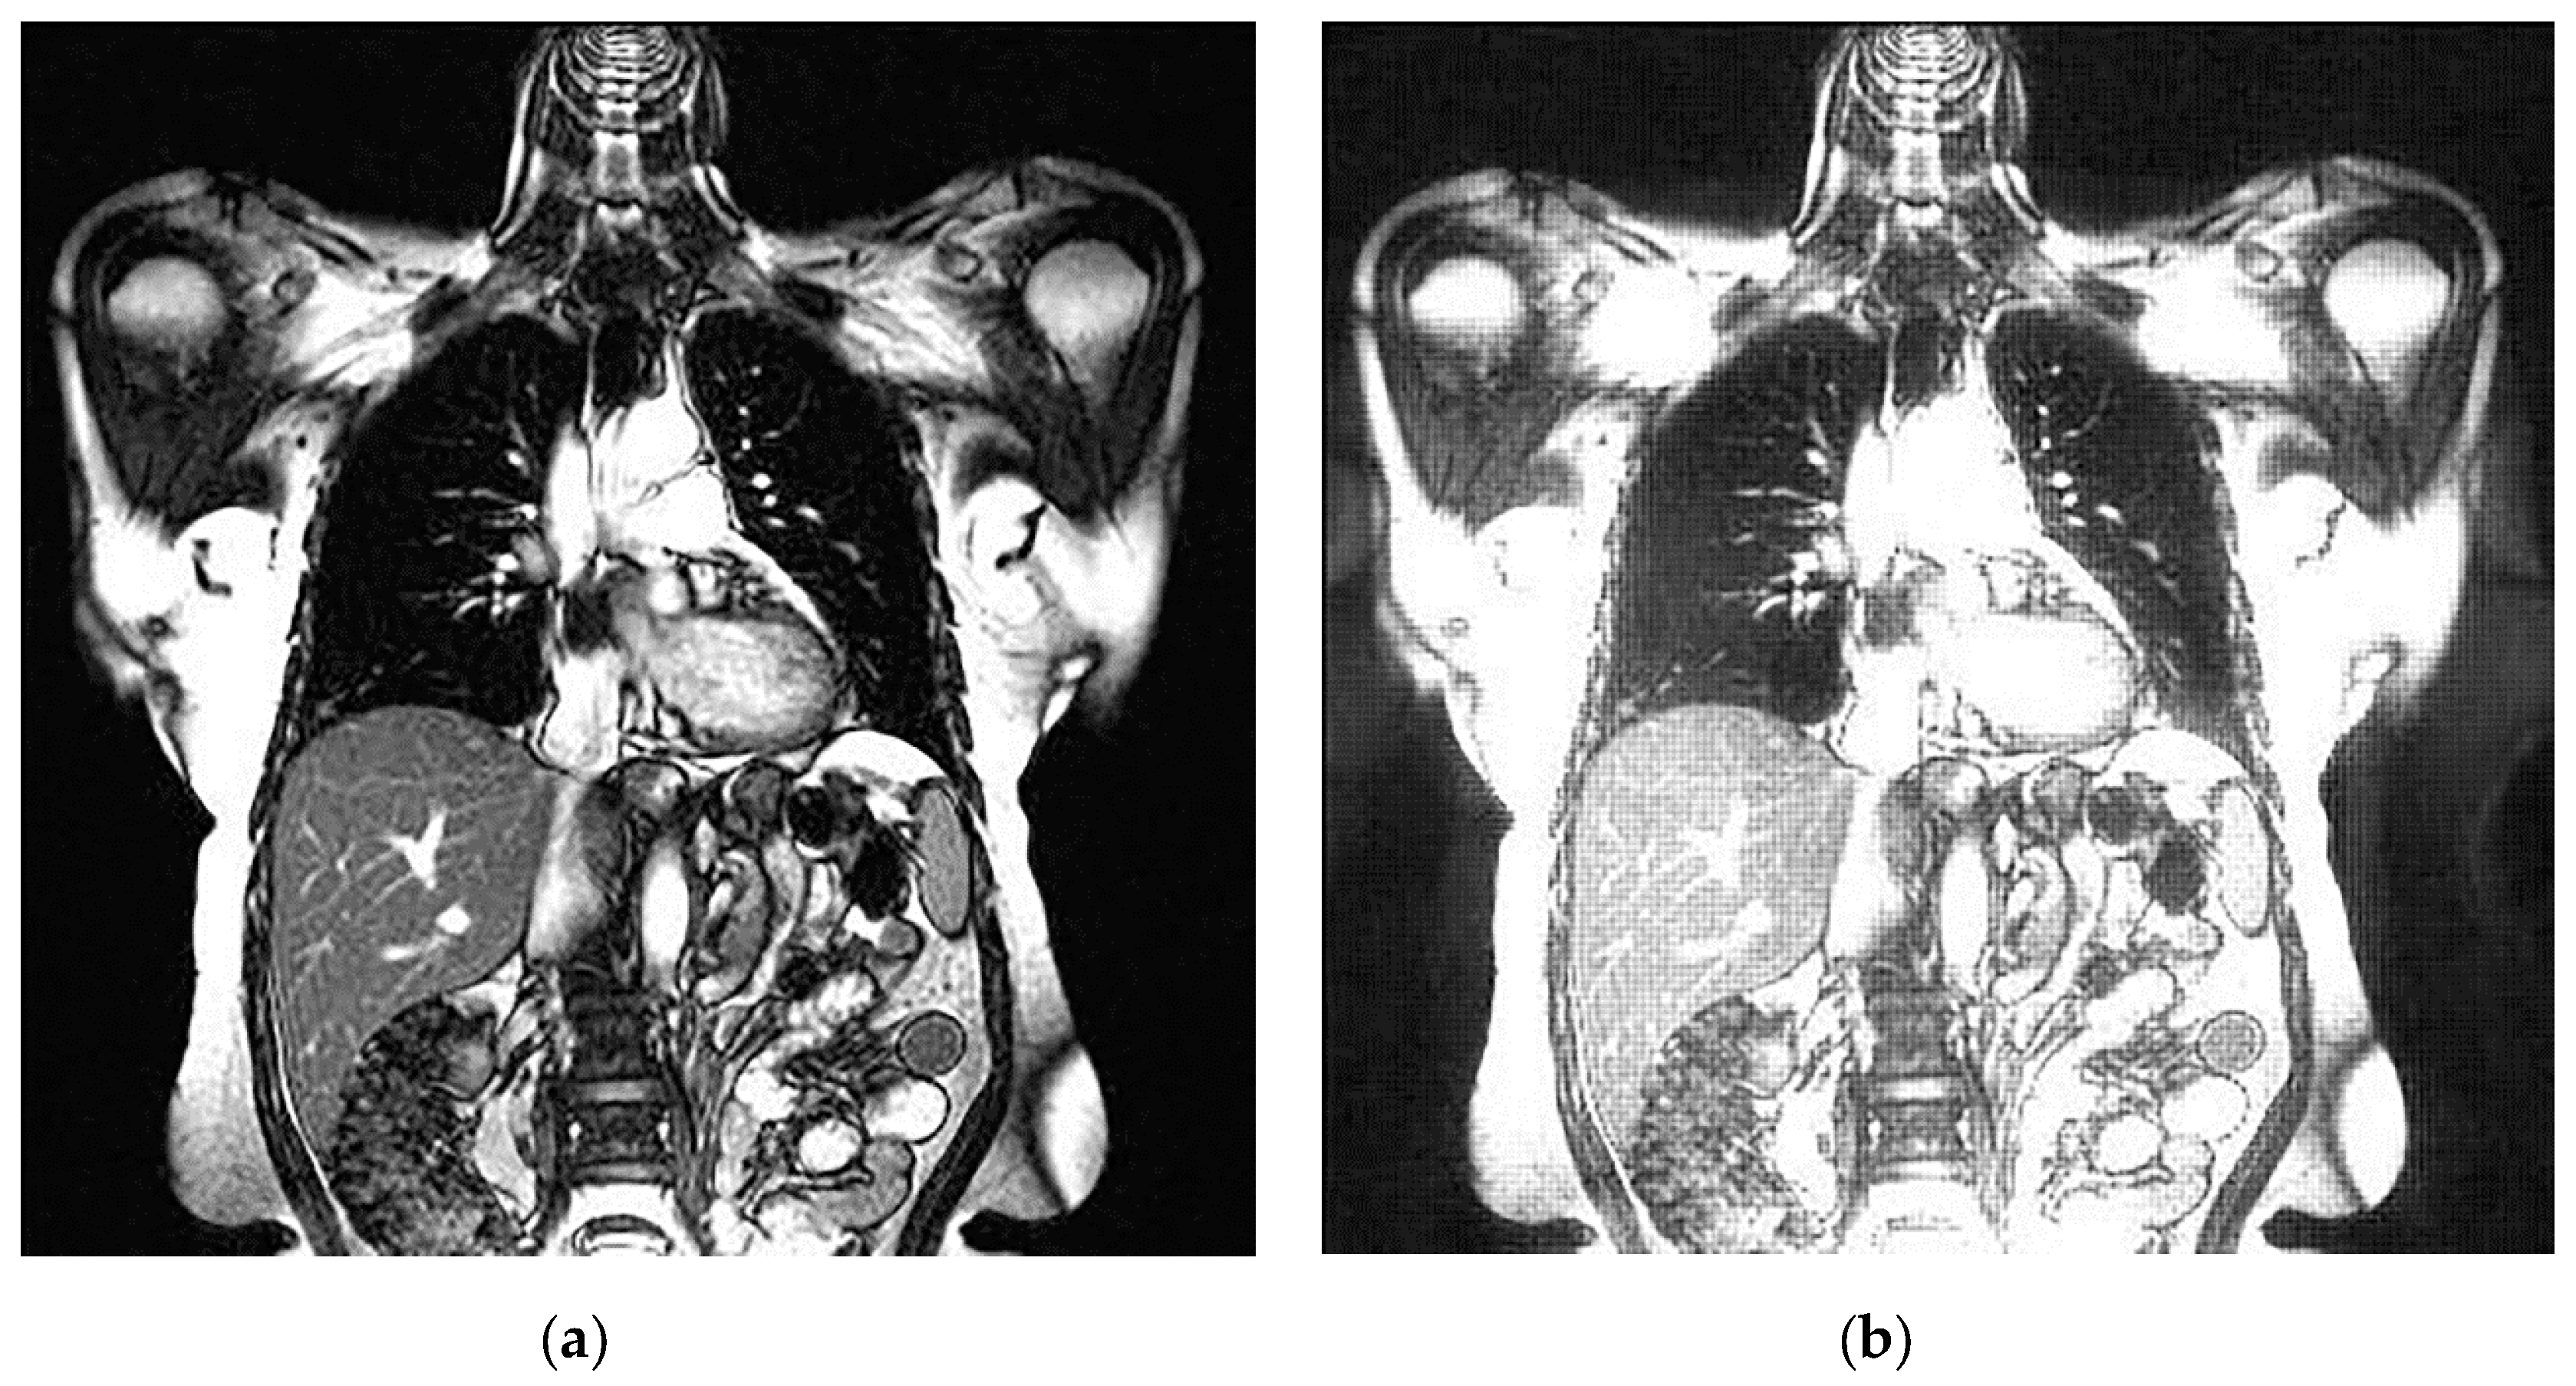

An example of 3D tomographic images “wmri”, “Trufi_COR” and “Body_1.0” DWT with wavelet d b 8 is shown in Figure 5, Figure 6 and Figure 7 respectively. Frames in Figure 6 and Figure 7 are selected to illustrate the error effect on the image processing result. Figures show a gradual improvement in the quality of processing with an increase the bit-width r : in Figure 5b, Figure 6b and Figure 7b visible distortion (Figure 5b is darkened in places, and Figure 6b and Figure 7b are lighted); in Figure 5c, Figure 6c and Figure 7c processed images are indistinguishable by eye from the original images; in Figure 5d, Figure 6d and Figure 7d processed images are identical to the corresponding originals. Experimental results are of higher quality compared with the calculation results. The values P S N R = 47.11 dB and P S N R = at r = 12 and r = 15 respectively (Figure 5) obtained after 8-bit image “wmri” DWT with wavelet d b 8 exceed the corresponding calculated values P S N R = 37.82 dB and P S N R = at r = 12 and r = 15 respectively (Table 1). The values P S N R = 64.57 dB and P S N R = at r = 12 and r = 17 respectively (Figure 6) obtained after 12-bit image “Trufi_COR” DWT with wavelet d b 8 exceed the corresponding calculated values P S N R = 36.67 dB, P S N R = 67.30 dB at r = 12 and r = 17 respectively (Table 2). Similarly, for “Body_1.0”.

Figure 6. Example of 3D tomographic 12-bit image “Trufi_COR” (15-th frame) DWT by d b 8 wavelet: (a) original image; processed image: (b) r = 7 , P S N R = 30.27 dB; (c) r = 12 , P S N R = 64.57 dB and (d) r = 17 , P S N R = .

Applsci 10 01223 g006aApplsci 10 01223 g006b